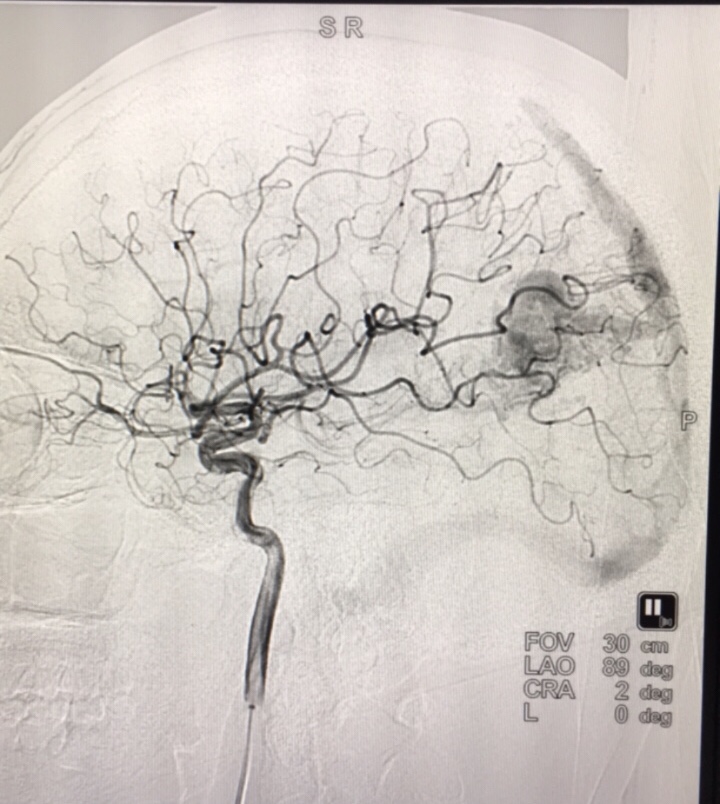

Hình ảnh dị dạng mạch máu não của bệnh nhân

Mới đây, Khoa ngoại Thần kinh (Bệnh viện Thanh Nhàn – Hà Nội) tiếp nhận bệnh nhân T.N.A 31 tuổi (quận Hai Bà Trưng - Hà Nội) trong tình trạng đau đầu vùng đỉnh phải buồn nôn, hoa mắt chóng mặt nhiều. Bác sĩ Phạm Quang Phúc - Trưởng khoa ngoại Thần kinh trực tiếp điều trị bệnh nhân, từ kết quả chụp đã kết luận bệnh nhân bị dị dạng mạch não và được can thiệp nút mạch túi phình động mạch não, điều trị tích cực. Hiện tại bệnh nhân đã ổn định.